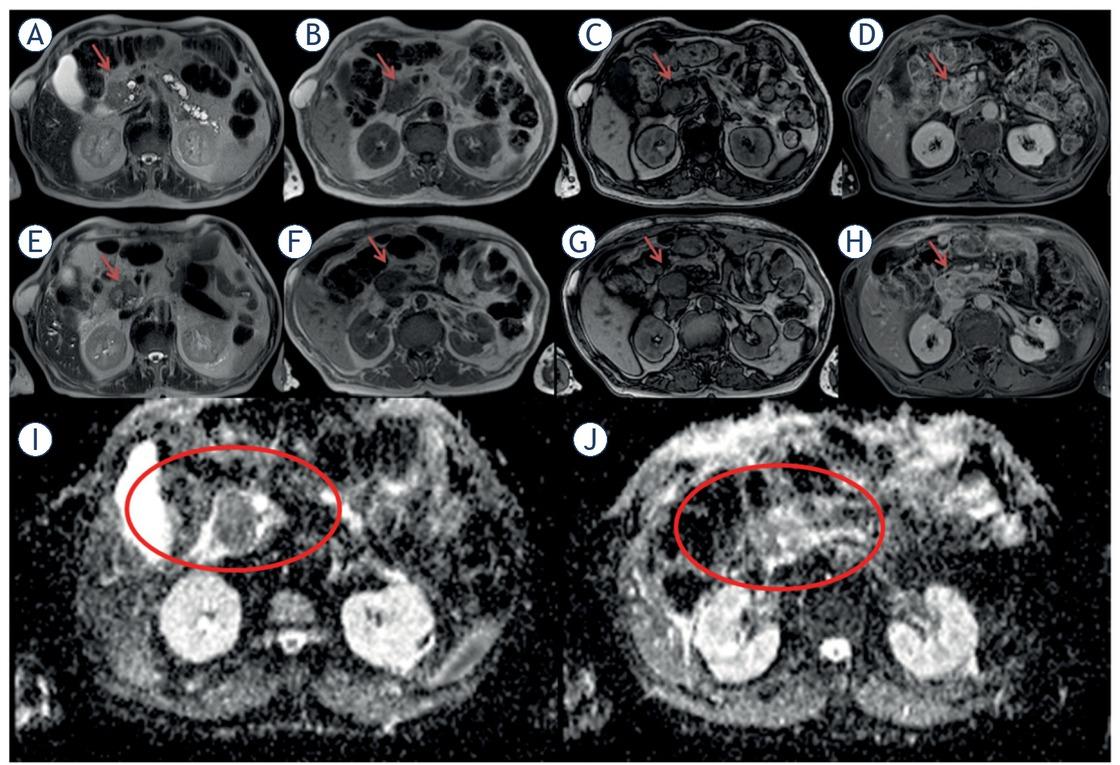

Figure 4 shows a case of significant response on conventional MR images, ADC map and DKI derived parameters maps.

Adenocarcinoma of the pancreatic head. Before treatment in (A) (half-Fourier acquisition single-shot turbo spin-echo [HASTE] T2- Weighted [W] sequence), the lesion (arrow) appears hyperintense, in (B) (in-phase T1-W sequence) and (C) (out-phase T1-W sequence) appears hypointense and hypovascular in (D) (volumetric interpolated breath hold examination [VIBE] T1-W in equilibrium phase). After the treatment the lesion in (E) (HASTE T2-W sequence), (F) (in-phase T1-W sequence), (G) (out-phase T1-W sequence) and (H) (VIBE T1-W in equilibrium phase): there were not significant differences in size and signal compared to baseline. Apparent diffusion coefficient (ADC) map before and after treatment (I, J).